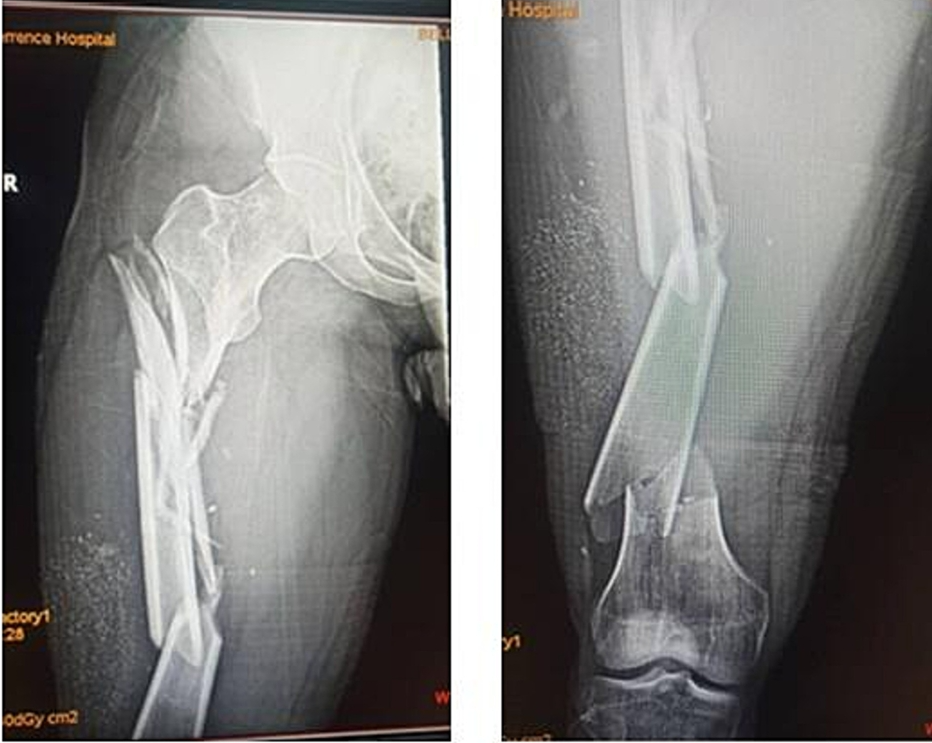

一,背景:复杂股骨骨折是指股骨干合并近端或远端骨折的复合型损伤,仅占所有股骨骨折的5%,治疗极具挑战性。单一内固定方案常难以实现有效固定,现有文献报道了多种治疗方式但疗效参差不齐。本病例报告展示了一例股骨近端严重粉碎性骨折合并远端节段性骨折的患者,其骨折极不稳定需手术治疗。据我们所知,此类复杂骨折类型在文献中极为罕见,关于其固定方式的报道几乎空白。本例采用微创双钢板重叠固定技术,分别于骨折区域上下方应用桥接型股骨近端锁定钢板与刚性股骨远端锁定钢板。二,案例:一名38岁男性患者因交通事故致右大腿闭合性损伤,表现为疼痛、畸形、肿胀及无法负重,至我院急诊就诊。患者为轿车后排乘客,车辆高速行驶时右侧遭受正面碰撞。查体见右大腿明显肿胀伴压痛。右大腿平片显示:右股骨近端节段性粉碎骨折合并远端两处横行骨折(图1)。采用微创钢板接骨术。经三个外侧切口显露股骨(图2)。采用间接复位技术,实现近端骨块的相对对位,并在透视引导下置入两块锁定钢板:股骨近端锁定钢板(PFLP)采用顺行置入,股骨远端锁定钢板(DFLP)采用逆行置入。两钢板重叠区域通过两枚皮质骨螺钉经对应孔道实现骨固定(图3)。术后给予镇痛药物、深静脉血栓预防及抗生素预防治疗,患者恢复顺利。引流管于术后第2天拔除,指导患者使用腋拐行走,右下肢禁止负重。术后第5天出院,嘱2周后返院拆线。在物理治疗师指导下,分别于术后6周及12周开始部分负重及完全负重行走。术后即刻X线片显示内固定位置良好(图4)。桥接钢板固定的近端区域可见四皮质骨痂形成,术后6个月(图5)及9个月(图6)X线片。远端节段性骨折线呈渐进性消失,术后9个月X线片显示骨折线完全消失(图6)。三,总结:此类复杂性股骨骨折属于罕见的高能量创伤。本文报道了采用微创双钢板接骨术成功治疗复杂股骨骨折的案例,结果显示骨折及时愈合且临床疗效良好。文献来源:Kabiru Salisu, Ifeanyi Kene Aghadi,Minimally invasive dual plating of a complex femoral fracture; a case report,Trauma Case Reports,Volume 43,2023,100768,ISSN 2352-6440, https://doi.org/10.1016/j.tcr.2023.100768.